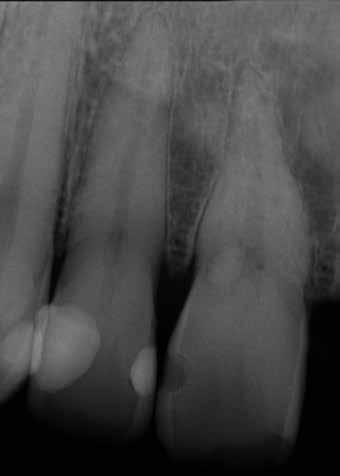

A maradó fogak gyökérreszorpciója patológiás folyamat. Az elváltozások elhelyezkedése alapján csoportosíthatjuk őket külső és belső reszorpciós folyamatokra. A külső gyökérreszorpciók egyre gyakrabban diagnosztizált formája a külső nyaki reszorpció (angolul External Cervical Resorption, ECR) [1. és 2. kép]. Az ECR egy komplex elváltozás, amely egyszerre érintheti a fog keményszöveti állományát, a parodontális szöveteket és előrehaladott esetben a pulpaszövetet is. A modern diagnosztikai eszközöknek köszönhetően egyre gyakrabban és egyre korábban kerül diagnosztizálásra ez a típusú lézió, így a kezelése is egyre inkább a mindennapi klinikum részévé válik az endodonciával foglalkozó kollégák számára. A 3 dimenziós diagnosztikai eszközök terjedésével felmerült az igény egy 3 dimenziós klasszifikációra. Patel és munkatársai 2018-ban kidolgoztak egy új klasszifikációt, amely segít az elváltozások kategorizálásában és a kezelések tervezésében [1]. A téma aktualitását jól mutatja, hogy ezzel egy időben az ESE (European Society of Endodontology) is kidolgozott egy állásfoglalást a külső nyaki reszorpciók diagnosztikájával és terápiás lehetőségeivel kapcsolatban [2].

Ötvenes éveiben járó páciensünk rutinellenőrzésre érkezett rendelőnkbe. A vizsgálat során felfigyeltünk a jobb felső metszőfogán kialakult, íny alatti elváltozásra. A röntgenfelvételen jól látható a kis méretű (Patel 1Ad) reszorpciós elváltozás [3. kép]

1. és 2. kép: Külső nyaki reszorpciós elváltozások CBCT képen.9. kép: Referáló orvos által készített röntgenfelvétel – 10. kép: CBCT felvételen 3 dimenzióban értékelhető a reszorpciós kavitás kiterjedése.